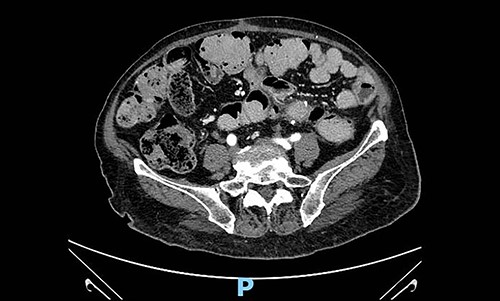

We present the case of a 79-year-old woman, whose clinical history reports hypertension, dyslipidemia, type 2 diabetes, obesity, tonsillectomy, open appendectomy, open hysterectomy and subtotal thyroidectomy. After an occasional finding of low haemoglobin level, the patient underwent a gastro-intestinal endoscopy with normal findings and subsequently complete abdomen contrast-enhanced-computed-tomography (CT) scan, which documented a solid mass in the left pelvic quadrant (sizes 84 × 92 × 110 mm) of uncertain origin. The mass was partially non-dissociable from the left round ligament and caused partial compression of the small bowel, without apparent invasion (Fig. 1). A diagnostic/curative laparoscopy was initially indicated. The patient entered the Emergency Room for sub-occlusive condition and was admitted to our Surgical Department. Sub-occlusion was treated conservatively and then, during the same hospitalization, the patient underwent open excision of the mass en-bloc with the colic segment and left adnexal tissues. Nasogastric tube was removed on post-operative day (POD) 1. Bowel opening to gas and stool occurred, respectively, on POD 3 and 4. Oral feeding was resumed on POD 3. Surgical drainage was removed on POD 7. The patient was discharged on POD 8.

Pre-operative abdominal contrast-enhanced CT scan. Solid mass in the left pelvic quadrant originating from sigmoid mesentery, partially non-dissociable from the left round ligament, is appreciable.